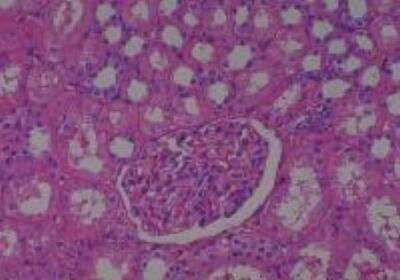

Scientific Data Images for Human Multi Tissue MicroArray (Normal Adjacent)

Hematoxylin & Eosin Stain: Human Common Tissue MicroArray (Normal Adjacent) [NBP2-30215] - 103. Stomach